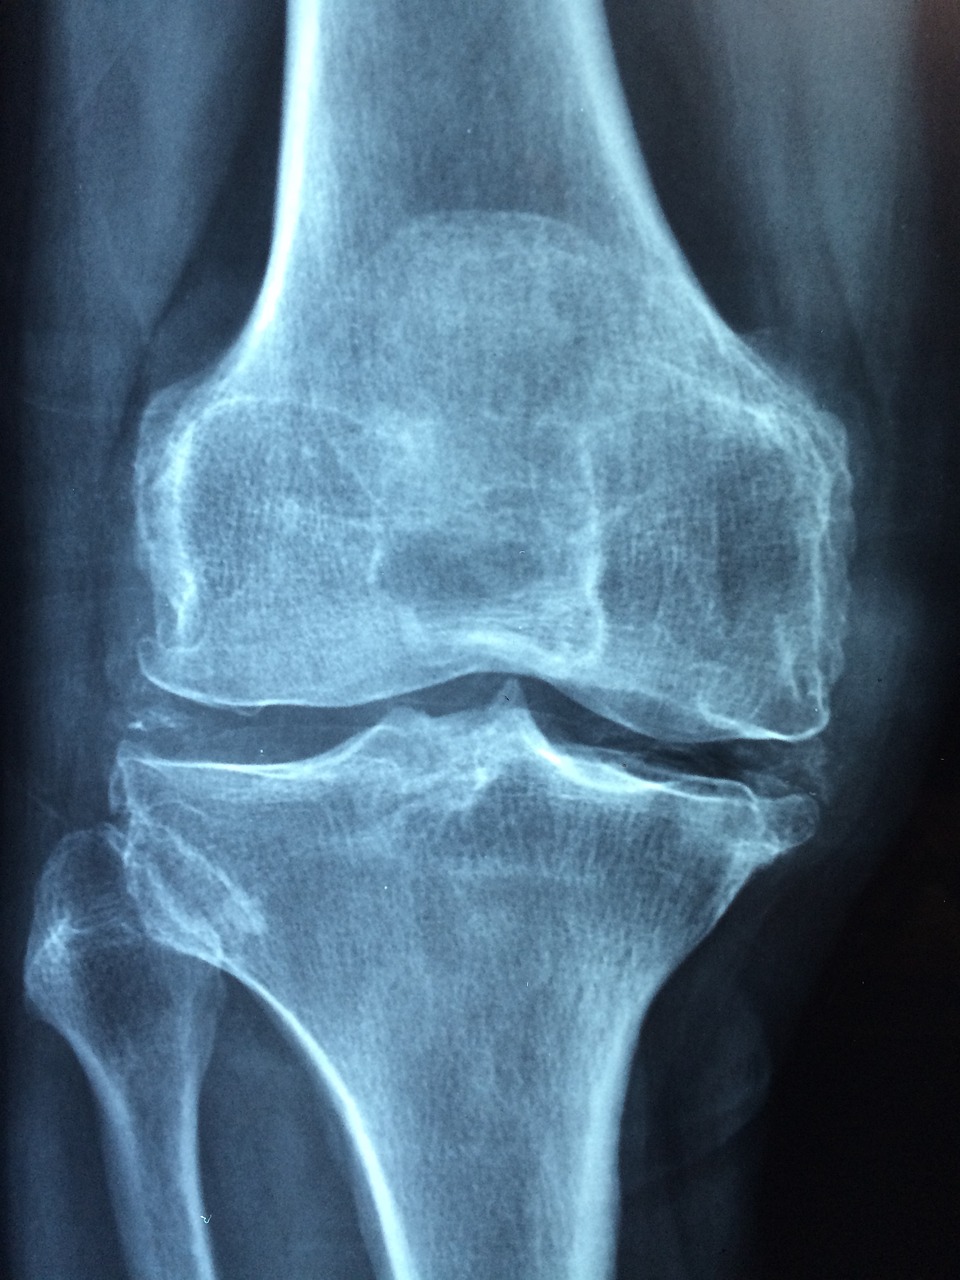

무릎 퇴행성 관절

무릎 안쪽에 통증이 생길 경우 노화로 인한 무릎 퇴행성 관절일 경우가 많습니다.

요즘은 심한 운동 등으로 30대 처럼 젊은 사람들도 퇴행성 관절염 등이 생기곤 하는데요, 연골과 뼈 사이에 마찰을 줄여주는 연골이 파괴되거나 염증이 생기는 경우 발생되며 약물치료나 물리치료 등이 듣지 않을 경우 수술이 필요할 수도 있습니다.

만약 무릎 뒤쪽 통증이 인대가 찢어진 경우라면 무릎 관절을 인공 관절로 교체하는 등 수술을 받을 수도 있습니다. 수술의 경우 긴 회복시간이 필요한 단점이 있는데요, 수술 이후에도 물리치료와 무릎을 이완시켜주는 스트레칭 등을 지속적으로 함께 해주는 것이 필요합니다.